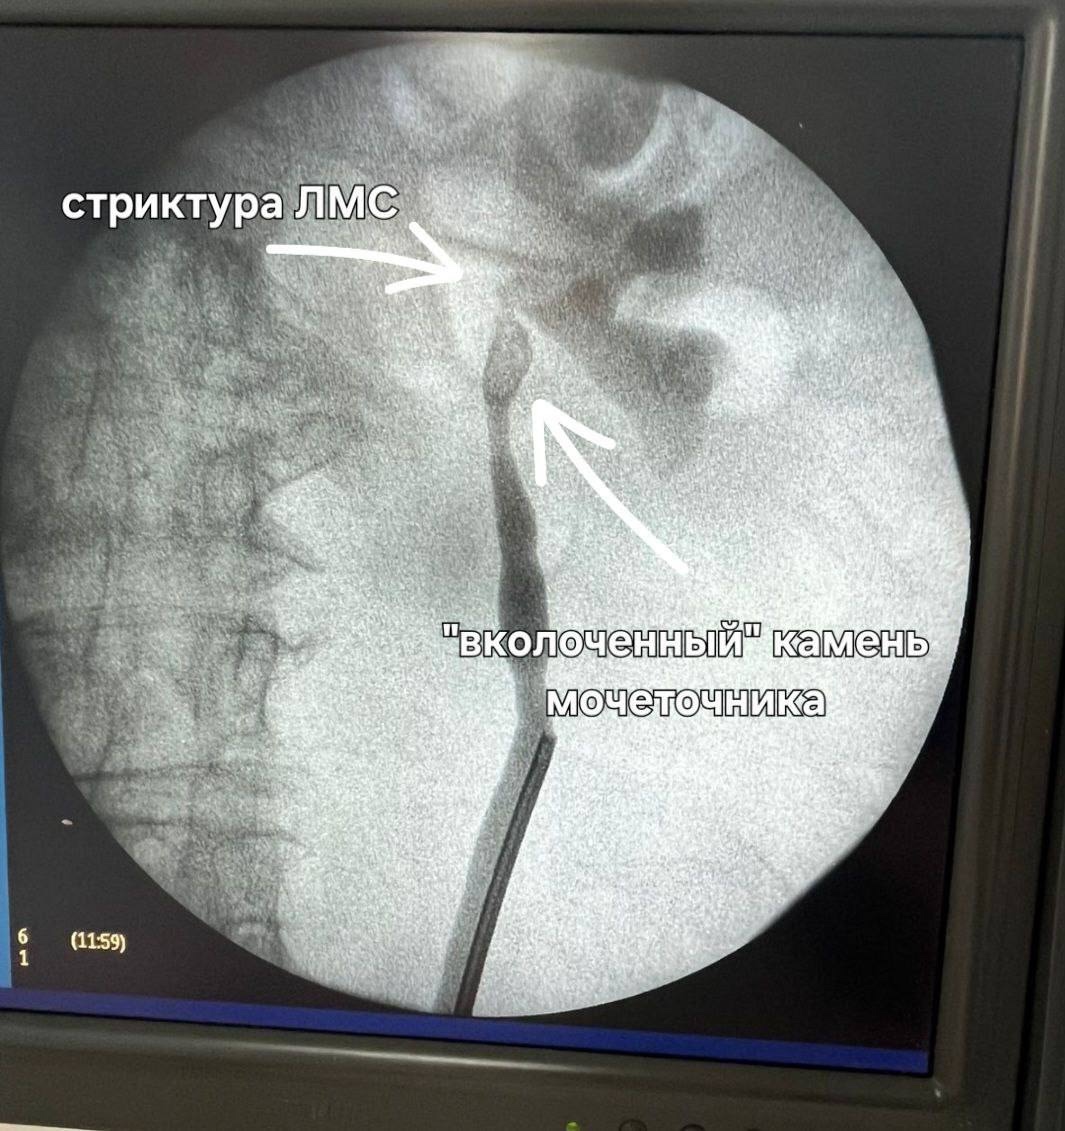

По словам заведующего отделением, операция была проведена возрастной пациентке с избыточной массой тела, у которой диагностировали «вколоченный» камень мочеточника, блокаду левой почки и стриктуру лоханочно-мочеточникового сегмента (ЛМС – сужение участка, где почка соединяется с мочеточником), вызванную длительным стоянием конкремента. Классическая ригидная уретероскопия в данном случае оказалась малоэффективной – из-за изгибов и выраженного сужения мочеточника камень не удалось визуализировать.

Использование гибкого фиброуретроскопа, инструмента с подвижным кончиком и камерой, позволило специалистам добраться до камня и точно направить лазер к любой его части. Благодаря установке мочеточникового кожуха (трубки для облегчения доступа инструментов) и активной ирригации, все фрагменты раздробленного камня были эффективно выведены наружу. Операция прошла успешно и с минимальной травматичностью для пациентки.